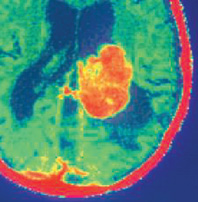

Các genee ung thư

Năm nay, các nhà khoa học đã gặt hái được những thành công ban đầu trong việc nghiên cứu những DNA khiếm khuyết đã làm cho các tế bào ung thư phát triển bất thường. Những nghiên cứu này đang hé lộ cho chúng ta bức tranh toàn cảnh về genee đối với những căn bệnh ung thư đặc biệt ở con người, mở ra những hướng mới trong chẩn đoán và điều trị.

Năm nay, các nhà khoa học đã gặt hái được những thành công ban đầu trong việc nghiên cứu những DNA khiếm khuyết đã làm cho các tế bào ung thư phát triển bất thường. Những nghiên cứu này đang hé lộ cho chúng ta bức tranh toàn cảnh về genee đối với những căn bệnh ung thư đặc biệt ở con người, mở ra những hướng mới trong chẩn đoán và điều trị.

Nhờ những sắp xếp rẻ hơn, các nhà nghiên cứu có thể quan sát một cách hệ thống sự thay đổi rất nhiều genee trong các tế bào ung thư mà các phương pháp trước trước đây không thực hiện được. Bởi vậy, những kết quả đầu tiên của các dự án về gene ung thư bắt đầu cách đây hai năm đã được công bố trong năm 2008.

Bằng việc sắp xếp hàng trăm, thậm chí hàng nghìn genee, các nhà khoa học đã xác định hàng chục sự biến đổi, trong đó có những biến đổi hoàn toàn mới. Chẳng hạn như một genee ung thư có tên IDH1 xuất hiện trong những khối u thần kinh đệm. Một nghiên cứu thần kinh đệm riêng biệt đã tiết lộ nguyên nhân tại sao các khối u của một số bệnh nhân phát triển ngừa thuốc. Những nghiên cứu khác cũng đã sàng lọc những DNA bất thường trong những khối u ung thư tuyến ở phổi và ung thư bạch cầu dạng tủy ác tính.

Việc mở rộng danh sách các genee gây ung thư sẽ mang lại những hy vọng mới trong chẩn đoán và phát triển các loại thuốc điều trị căn bệnh quái ác này.